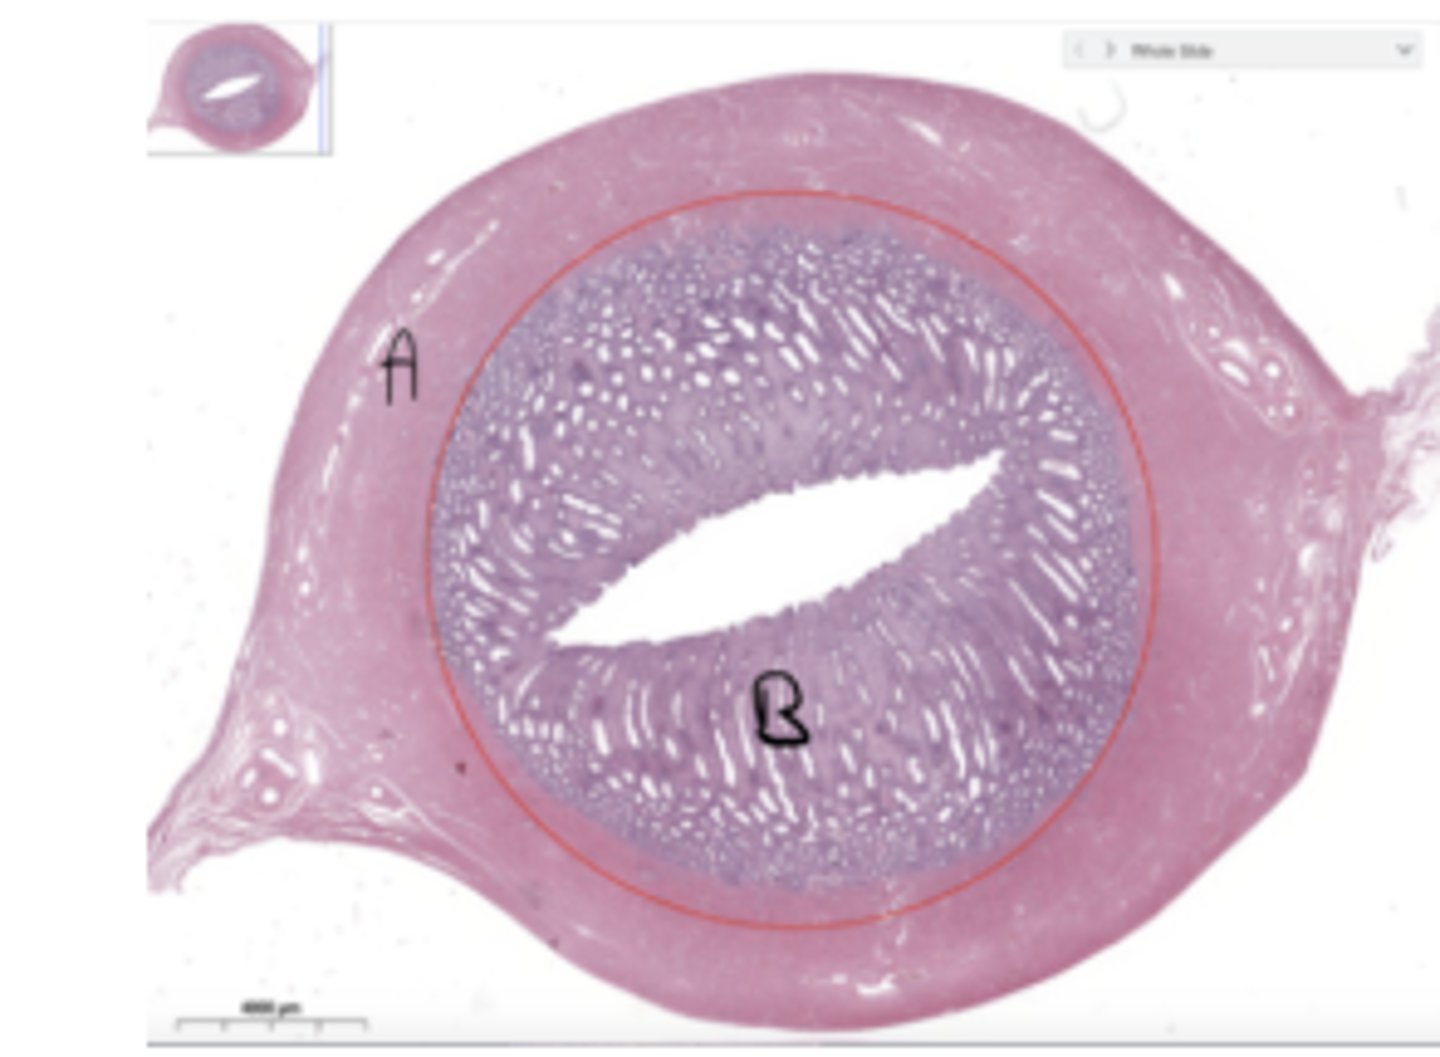

Corpus cavernosum

What contributes to the main source of rigidity during an erection

red: corpora cavernosa

seminiferous tubules